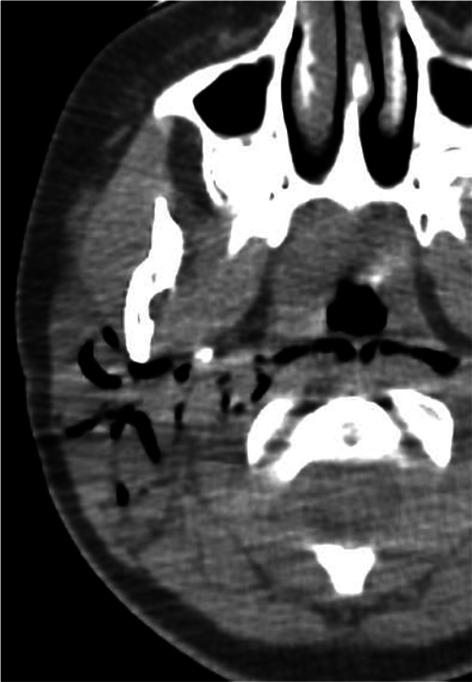

在婴幼儿及儿童时期,多种疾病可累及腮腺。急性或慢性炎症/感染性疾病最为常见。第一鳃裂畸形是先天性病变,通常在儿童期出现。肿瘤性病变多为良性,婴儿期最常见的是婴儿血管瘤,儿童期最常见的是多形性腺瘤。恶性肿瘤并不常见,黏液表皮样癌相对多见。腮腺浸润性疾病罕见,且具有一些儿科临床特点。本文对儿童期腮腺这些常见和不常见疾病及其影像学特征进行综述。